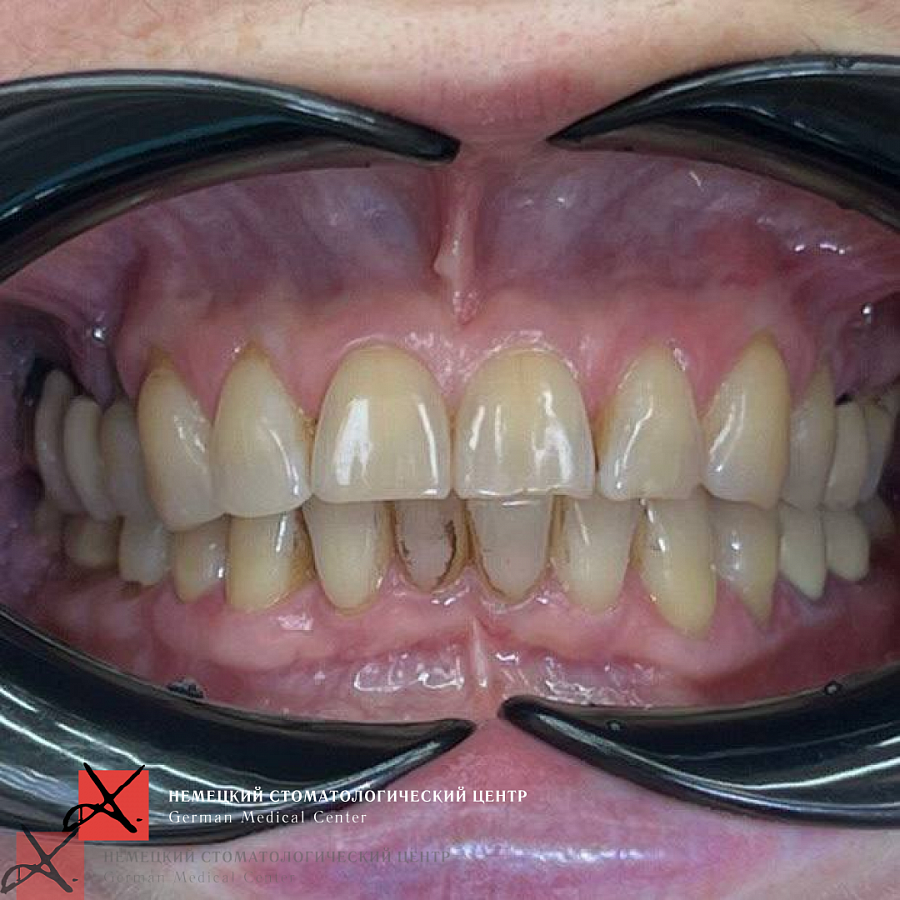

Что получили?

рот открывается без проблем

ушли боли в ВНЧС, нормализовался тонус жевательных мышц

Ждём результаты после протезирования!

Результат лечения